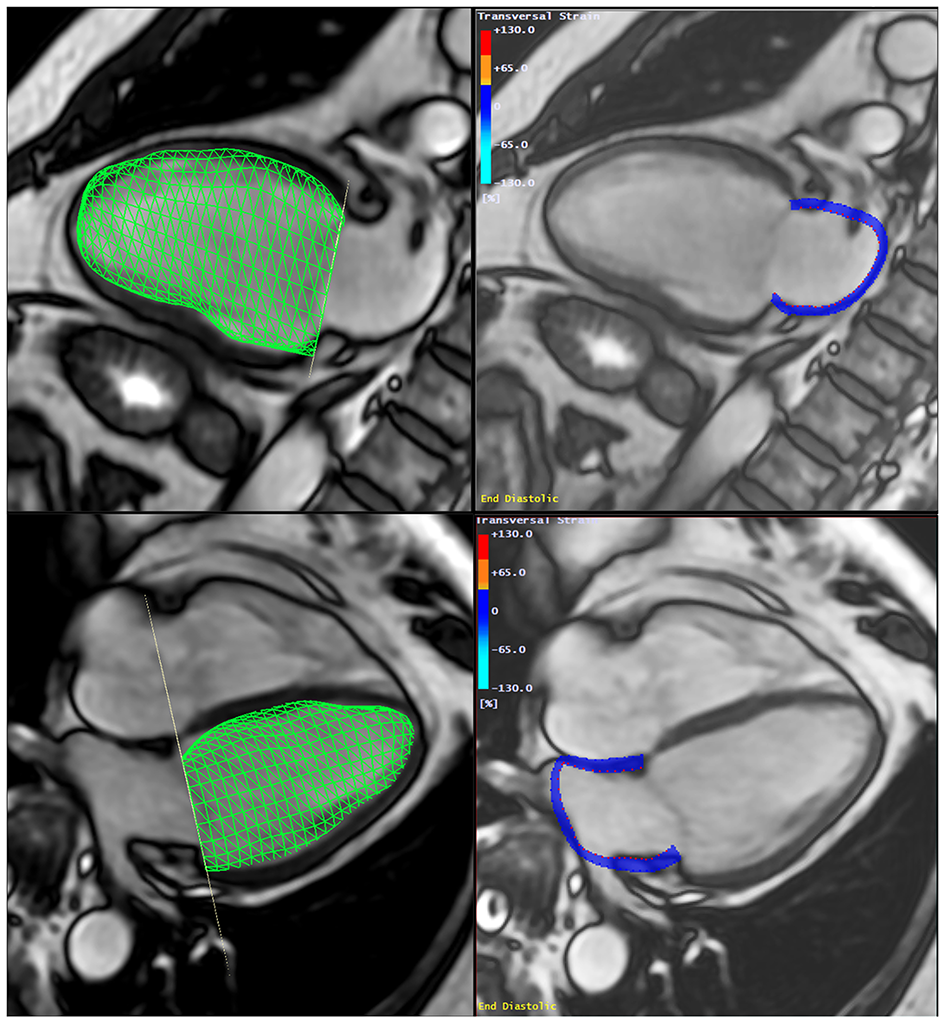

The LACI was defined by CMR for each participant by the LA end-diastolic volume divided by the LV end-diastolic volume. The LV volume was measured from the stack of short-axis cine images, while the LA volume was measured from the 2-chamber and 4-chamber views, as previously described (Figure 2). The LA and LV volumes were measured in the same end-diastolic phase defined by mitral valve closure.

Figure 2

Method to assess the Left Atrio-ventricular Coupling Index (LACI) by CMR. The LACI was defined by the ratio between the LA end-diastolic volume and the LV end-diastolic volume. A stack of short-axis cine images was acquired to encompass both ventricles and LV end-diastolic volume was measured using cardiac image modeler (CIM) software (green volume, left panel). LA end-diastolic volume was measured using multimodality tissue-tracking (MTT) software to track LA wall motion during the end-diastole in the 4-chamber and 2-chamber views (pink borders, right panel). CMR, cardiovascular magnetic resonance; LA, left atrial; LACI, left atrioventricular coupling index; LV, left ventricle.